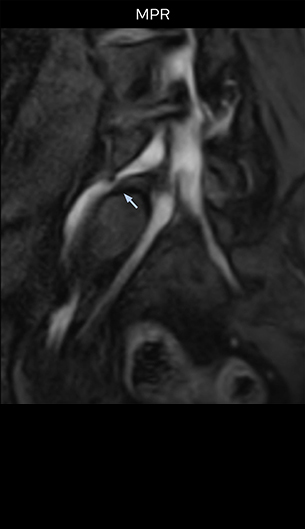

“In such case, we would then browse through axial T2-weighted MR images slice by slice and mentally reconstruct the actual situation based on both radiculography and MRI. Fortunately, NerveVIEW can now very well show nerve courses and presence of nerve compression or edema in one single image series.” “We have often seen NerveVIEW directly depict details of the nerve compression that were not observed by radiculography. Therefore, we think that with NerveVIEW we can reduce the number of invasive examinations, especially for some patients with lumbar plexus symptoms.”

“Before NerveVIEW, diagnosis by MRI alone was sometimes difficult, unless there was a strong suspicion based on clinical symptoms,” says Shoji Yabuki, MD, DMSc, Orthopedic surgeon at Fukushima Medical University School of Medicine. “This is why we routinely perform selective lumbosacral radiculography (nerve root block) and x-ray in such cases. However, radiculography can only depict nerves as far as the contrast agent reaches. When a nerve is distorted by compression, the contrast agent will not pass through this compressed area, preventing us from evaluating the full nerve compression.”

The key concept in MR neurography, Dr. Yabuki stresses, is the ability to directly visualize spinal nerves, versus inferring the presence of pathology indirectly. “Before NerveVIEW, we estimated compression of the nerve by looking for the presence or absence of fat signal on other MR images,” he says.

“For example, in sagittal images, when the presence of fat is observed in the intervertebral foramen, it suggests that there is a margin around the nerve. Similarly, the absence of fat indicates that the nerve is being compressed. So, we used to deduce nerve compression indirectly. With NerveVIEW, however, we can observe the condition of the nerves directly, regardless of the presence or absence of fat. We always prefer such direct observation of anatomy over having to make an inference about it.”

“The intra-luminal signal of veins, especially around the intervertebral space, can be suppressed well with NerveVIEW. As a result, we can easily observe the detailed nerve structure around the posterior ganglion,” he says. “This is why we use 3D NerveVIEW for intraforaminal stenosis and extraforaminal stenosis/herniation (lateral disc herniation). On the other hand, if herniation is suspected to exist inside the dorsal root ganglion (DRG), balanced TFE or ProSet-FFE is applied. NerveVIEW is not suitable for evaluating the median type of herniation.” The SE-EPI DWI-based method for MR neurography works well for large FOV exams like whole-body MRI, but focal examination of nerves is often limited by the attainable spatial resolution (both inplane and slice direction) and geometric distortion. “3D NerveVIEW achieves higher in-plane resolution – close to our other routine spine sequences – and the source images can be used instead of adding a fat-suppressed T2-weighted sequence,” Tanji says.